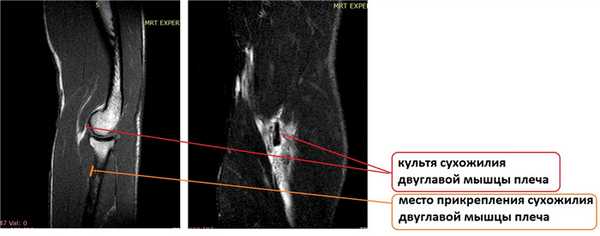

На МРТ диагноз отрыва дистального сухожилия двуглавой мышцы плеча был подтверждён. На представленных выше снимках отчётливо визуализируется оторванное сухожилие двуглавой мышцы плеча.

Пациенту предложено оперативное лечение, реинсерция сухожилия к лучевой кости по методике Артрекс (Arthrex). Отличиями данной методики является использование специальной пуговицы с направителем, выполнение операции из одного хирургического доступа, а также внутрикостное расположение сухожилие за счёт формирования в лучевой кости слепо заканчивающегося канала такого же диаметра как прошитое сухожилие. По нашему мнению данная методика позволяет добиться мощной первичной фиксации и ускоренного процесса прирастания сухожилия к кости за счёт его внутрикостного расположения.